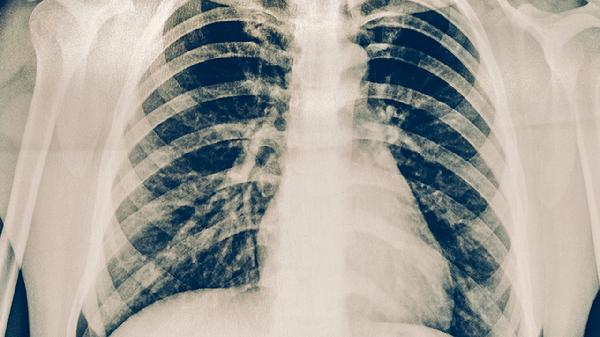

胸部CT显示磨玻璃影或小叶间隔增厚等典型表现时,即使无症状也提示存在亚临床感染。此类患者发生肺纤维化风险较常人高3倍,建议进行至少14天的克拉霉素治疗并定期复查影像。